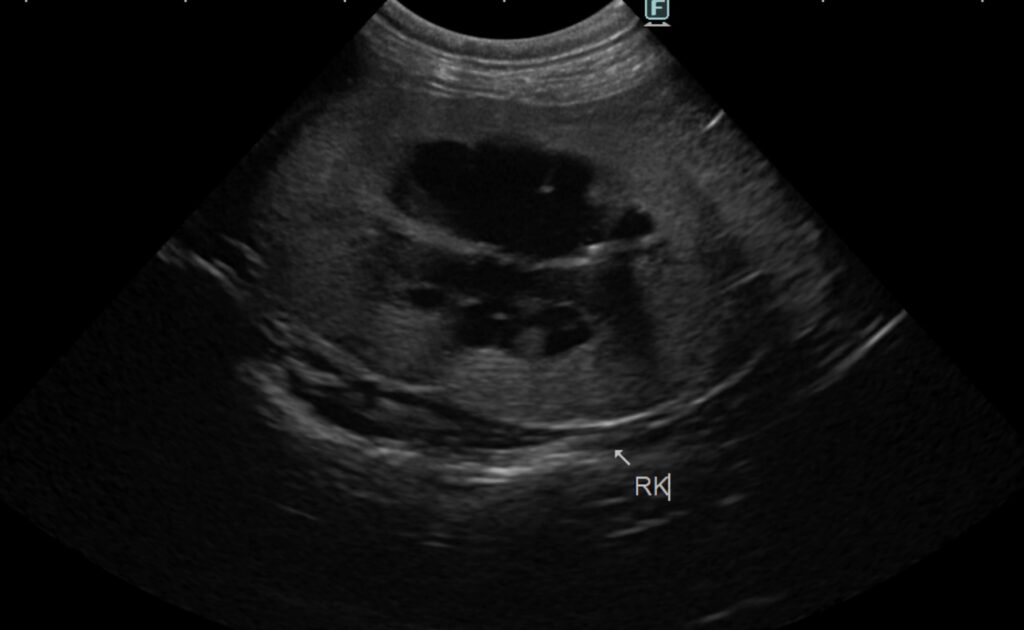

エコー検査より、両側の重度腎盂拡張、右腎臓の尿管拡張の所見が認められる。

右腎臓は6cm大に腫大、左腎臓は2cmに萎縮。